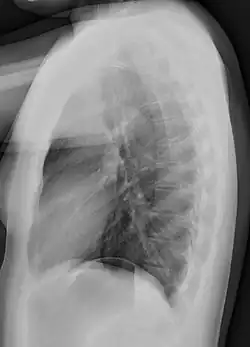

Lateral views of the chest are obtained in a similar fashion as the posteroanterior views, except in the lateral view, the patient stands with both arms raised and the left side of the chest pressed against a flat surface.

Typical views

Required projections can vary by country and hospital, although an erect posteroanterior (PA) projection is typically the first preference. If this is not possible, then an anteroposterior view will be taken. Further imaging depends on local protocols which is dependent on the hospital protocols, the availability of other imaging modalities and the preference of the image interpreter. In the UK, the standard chest radiography protocol is to take an erect posteroanterior view only and a lateral one only on request by a radiologist.[5] In the US, chest radiography includes a PA and Lateral with the patient standing or sitting up. Special projections include an AP in cases where the image needs to be obtained stat (immediately) and with a portable device, particularly when a patient cannot be safely positioned upright. Lateral decubitus may be used for visualization of air-fluid levels if an upright image cannot be obtained. Anteroposterior (AP) Axial Lordotic projects the clavicles above the lung fields, allowing better visualization of the apices (which is extremely useful when looking for evidence of primary tuberculosis).